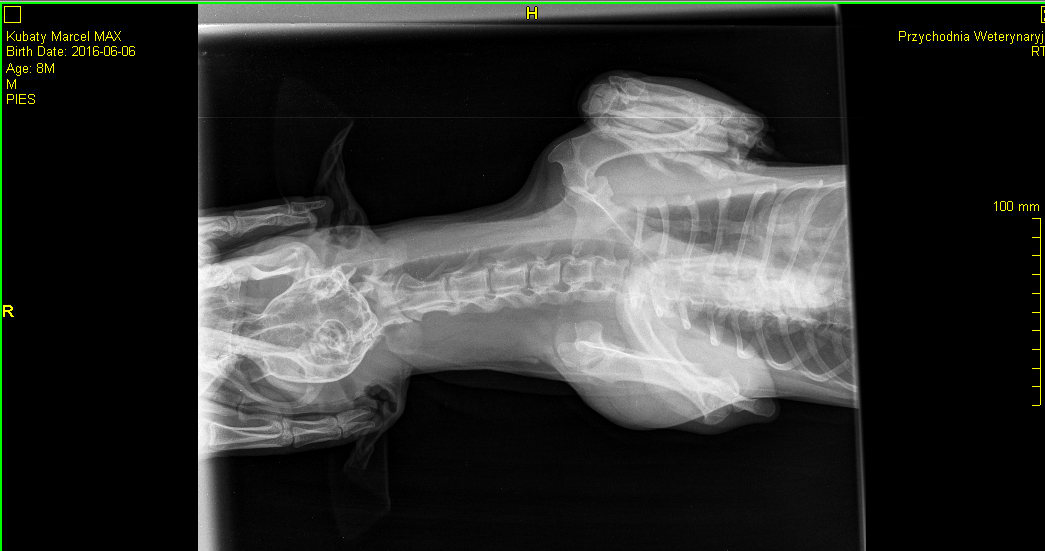

My dog (8-10 months old, small breed , similar to dachschund) had a problem with breatching - he had a dyspnoea attacks, he was exhaling with a lot of effort. he had rhinoscopy and was diagnosed with some kind of acute inflammation of soft palate. Now he is taking Prednisone 1mg/kg and the attacks are gone, but when i try to go down with the dosage, the attacks come back. Is there something that can cause such a state? I'm not sure whether Prednisone will eliminate the cause.... Greetings

Some dogs will have an elongated soft palate that can become inflamed, and prednisone helps reduce inflammation. Dachshunds are also more likely to develop a disease called lymphocytic-plasmacytic rhinitis that causes chronic nasal inflammation. This disease is usually diagnosed by taking biopsy samples during a rhinoscopy. In either case, the prednisone would probably not completely eliminate the disease and some kind of medication might be needed long term. I would recommend discussing treatment options with your veterinarian. I think his chest x-rays look normal for his breed.